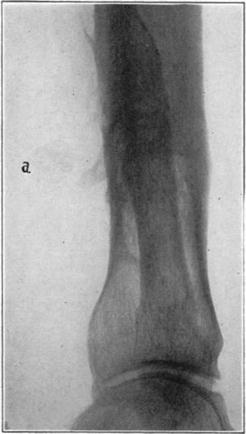

Case 4. Large splinter (a) displaced into soft parts from fresh fracture of tibia.

Case 4. The same (a) seven years later, showing reduction in size of splinter and apparent replacement by very spongy new bone.

Case 5. Tibial graft thirty-nine days after insertion in humerus.

Case 5. Ten years and eight months after operation. Shows non-functioning portion of graft in medullary cavity practically unchanged, but the functioning portion above hypertrophied and transformed.